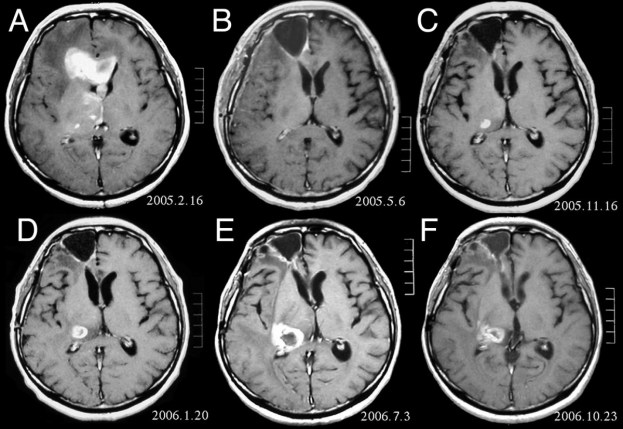

But, like many instances in Africa, when there is a problem, a solution is just around the corner. Johnes Obungoloch, who lectures at Mbarara University of Science and Technology, found a way of bringing the cost down of MRI scanners, which will therefore pass on the saving to the patient. MRI scanners use strong magnetic fields and radio waves to produce detailed images of the inside of the body. They are expensive machinery due to the strong magnetic field, its technical and infrastructural requirements, and at 5 tonnes, their massive weight.

By using ordinary copper wiring in his machine, and bringing the weight down to just 125 kgs, Obungoloch believes he will be able to cut 90% off the price to use the machine. Local staff will be trained how to repair and maintain the machine, further cutting down on costs. It is not quite ready yet, and will be needed to be tested on animals at first, but it should be ready to go in the next 2 years, cutting medical bills for cancer patients and those with other internal problems, drastically.